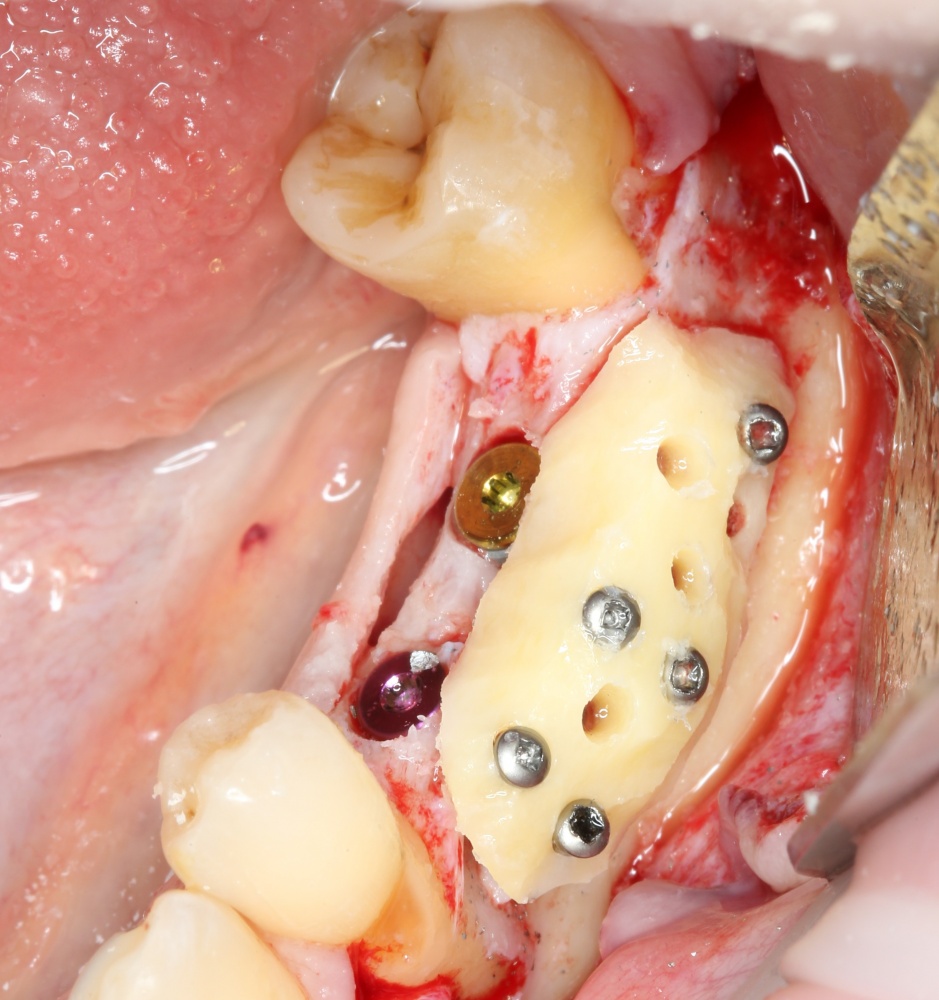

Фиксация костного блока:

A09A5452 (2) A09A5453 (2)

Для этого стоит использовать длинные винты. В противном случае, при подготовке лунки под имплантат костный блок может отлететь.

Переставляя винты и пришлифовывая аутокостный фрагмент, можно добиться более-менее точного соответствия принимающему ложу:

A09A5457 (2) A09A5458 (2)

Теперь можно готовить лунки под импланты:

A09A5459 (2)

В данном случае я планирую установить импланты Nobel Replace Conical Connection:

A09A5461 (2) A09A5462 (2)

Операция почти закончена. Обратите внимание, на два момента:

1. Блок явно больше, чем нужно. Это связано с тем, что в процессе интеграции происходит атрофия графтов (причем, абсолютно любых), и мы должны закладывать этот уровень атрофии при планировании объемов костной пластики. В среднем, плюс 30% к тому, что нам нужно.

2. Между блоком и принимающим ложем есть пустое пространство. Поэтому область операции необходимо изолировать барьерной мембраной от быстро растущих мягких тканей. Я использую Geistlich BioGide 25×25 mm:

A09A5466 (2) A09A5467 (2)